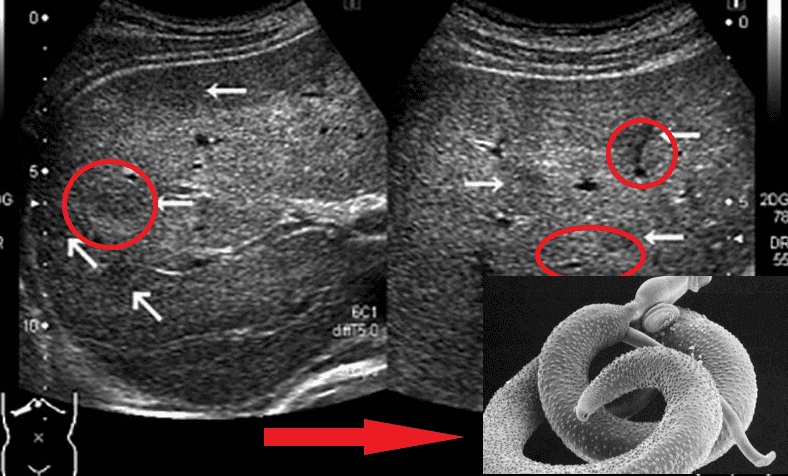

Представниками гельмінтів, що вражають життєво важливі органи, є Taenia solium, ехінокок (Echinococcus granulosus), трихінела (Trichinella spiralis). Ехінокок являє собою личинкову стадію гельмінта з роду Echinococcus. І це далеко не всі види паразитів, здатні убити людину.

О.Ю. Гришин: Так воно і є насправді. Практично в 90% випадків, коли я роблю розтин, бачу страшну картину. Тіла померлих кишать паразитами! І я спостерігаю їх не тільки в шлунково-кишковому тракті, як багато хто думає. Паразити часто живуть у легенях, серці, печінці й навіть у мозку! Їхні колонії населяють внутрішні органи, а личинки харчуються тканинами живих людей!